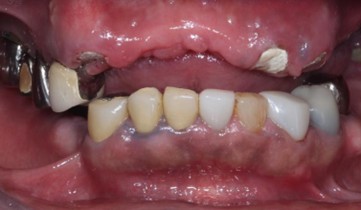

40代 女性

(薬・注射・レントゲン・CT・データ分析・骨造成・サージカルステント・血液検査) - 年齢/性別

- 40代/女性

- 患者の具体的な症状

- 左上6欠損のため義歯を使用していたが、噛むと痛みがあり不快なため、インプラント治療を希望

- 検査方法

- コーンビームCT、レントゲン撮影

- 診断結果

- 左下6欠損

- 治療詳細

- コーンビームCTによる画像診断で垂直的な骨高が不足し骨密度が少ないため、ソケットリフトによる骨再生治療とインプラント埋入を同時に行った。

- 通院回数

- 7回

- 治療期間

- 7か月